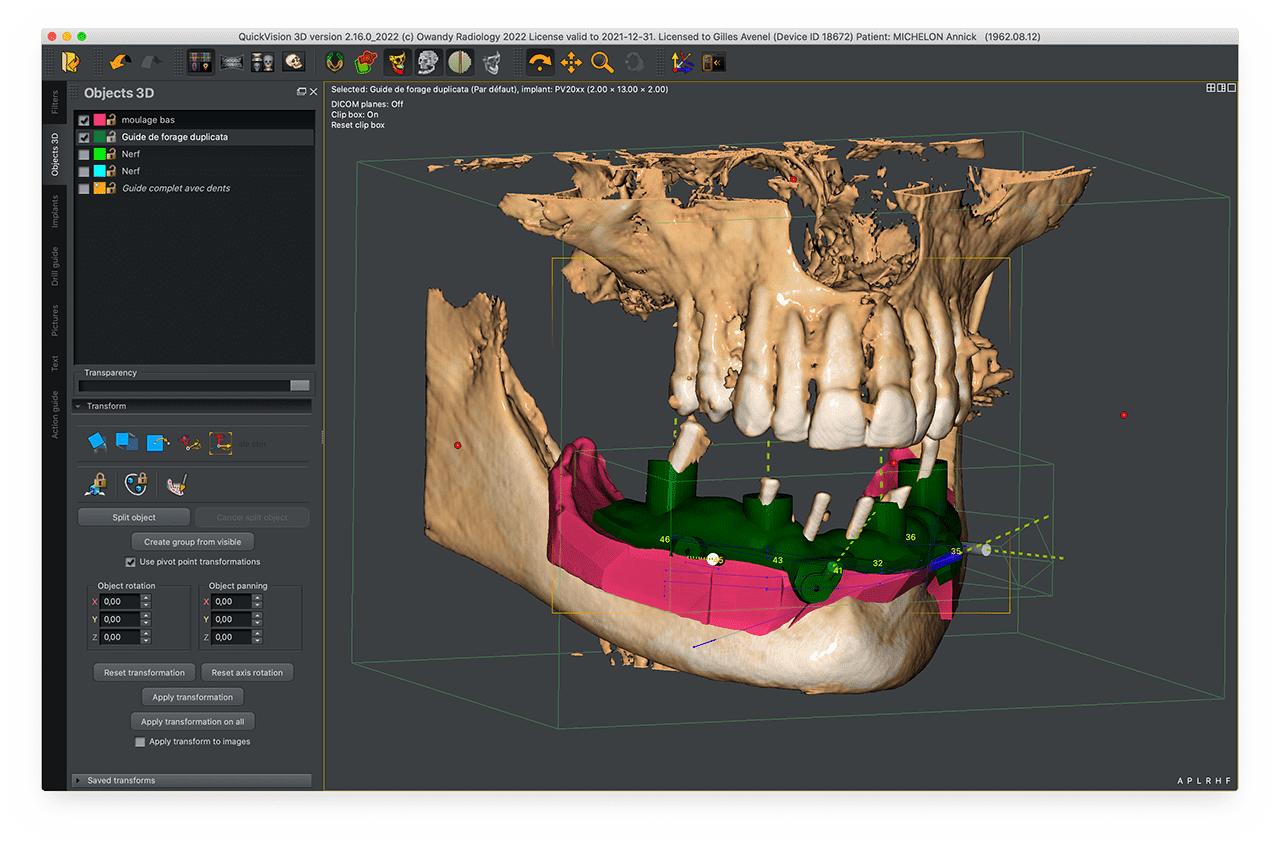

Place your implants, overlay your digital impressions, and create your own surgical guides.

It will allow you to define the types of implants and their specifications by choosing from a large library or simply creating it. You can also import 2D panoramic x-rays, digital optical impressions, scans of trays and other plaster casts.

Digital Wax-up

The software superimposes the two 3D objects.

This alignment will facilitate and bring precision in the design of the surgical guide during the following steps thanks to the integration of the soft tissues on the model.